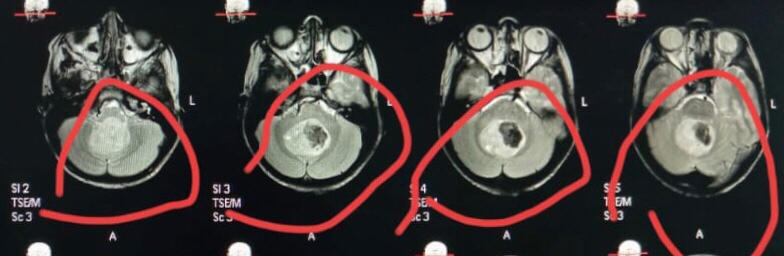

وأضاف الدكتور أحمد كمال مدير مستشفى الجراحات المتخصصة انه بعد عمل اشعة الرنين المغناطيسي تبين وجود ورم خبيث بالفص الخلفى من المخ ضاغط على المخيخ وجزع المخ، لافتاً الي أن هذة الحالات تعتبر من أخطر حالات أورام المخ وقاع الجمجمة لما يحمله الجزء المصاب به الورم من مراكز حساسة.

وأكد الدكتور عابدين خيرالله قاسم رئيس قسم جراحة المخ والأعصاب، أن الفريق الطبى الجراحى نجح في استئصال الورم كلياً مع الحفاظ على المراكز والشرايين المحيطة بالورم للحفاظ على المخيخ وجذع المخ، اعقبها نقل المريض الى العناية المركزة للأطفال لإفاقة الطفل تدريجياً، وبعد مرور يوم كامل للإفاقة استعاد الطفل الوعى كاملاً مع حركة الأطراف طبيعياً.